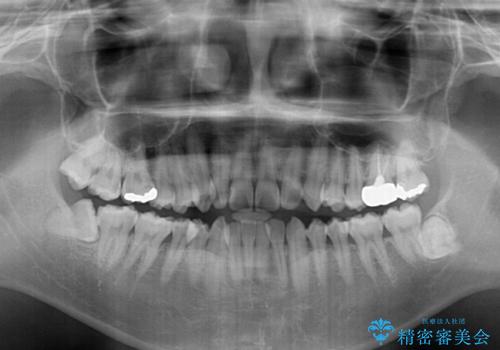

- 前歯のデコボコを気にして来院された患者様です。

前歯が90度近く捻れていたため、しっかりと治すことを考えるとワイヤー矯正の方がおすすめではありましたが、本人の希望によりインビザラインを用いて矯正治療を行うこととしました。

途中2年強の来院がなく、改善されていたデコボコが元に戻ったり、装着時間が不足しており前歯のデコボコは十分に改善することはできませんでしたが、5年間の有効期限内で可能な限り歯列を整えることができました。